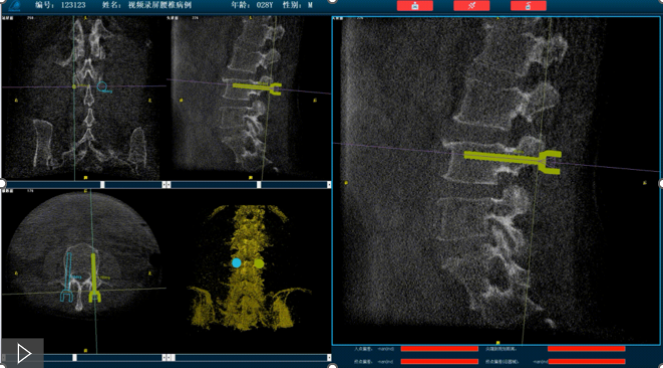

骨科機器人路線規劃

首先,需要明確的是機器人手術,機器人在術中還是做輔助性操作,術前基于三維C形臂等影像掃描得到骨骼結構的三維數據,機器人系統利用手術規劃軟件,引導醫生進行可視化預手術規劃(釘道規劃、入釘角度),選擇合適的螺釘規格、尺寸,輔助評估和及時調整手術路徑規劃設計,整臺手術都是在主刀醫生的把控下進行操作的。機器人系統不僅靠譜,而且還提升了手術的安全性、機械臂的精準以及力傳感識別、實時動態追蹤等保護技術,增加了手術的準確性和安全性。

就以普愛醫療骨科機器人PL300B為例,骨科機器人可以保證亞毫米級精準度,例如在脊柱上植入椎弓根螺釘,傳統手術需要暴露骨組織解剖結構,往往會有10-20cm的開口,而使用了手術機器人可以將開口轉變為數個1-2cm的開口,出血量降低至95%以上,大大降低并發癥的發生率,同時有益于病患的更快的術后恢復。